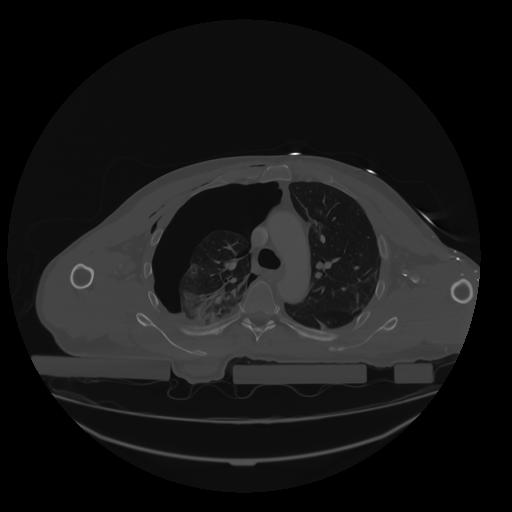

28 CUERPO,CE,Vol,2.0,CUERPO,,